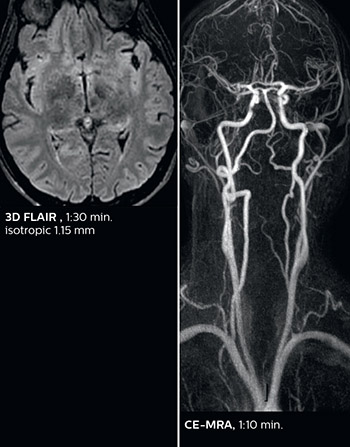

This is an example of acute ischemic stroke with distal occlusion of the right posterior cerebral artery. Note the improved visibility of the ischemic territory on the diffusion weighted image with high b-value. The 3D FLAIR shows a distal PCA occlusion. The fast SWIp depicts the thrombus on the isolated second echo image. The total scan time (including SmartBrain, preparations and a fast 3D T1w TSE Gd) is 8:00 minutes.

In this patient with acute right motor deficit and aphasia, the b2000 diffusion weighted image is normal. The SWIp image demonstrates more prominent veins in the right hemisphere, which could reflect increased deoxyhemoglobin contents. Fast ASL shows low CBF regions in the left frontal lobe. A follow-up ASL after one hour demonstrates high CBF values in the same area. The final diagnosis was migraine with aura.